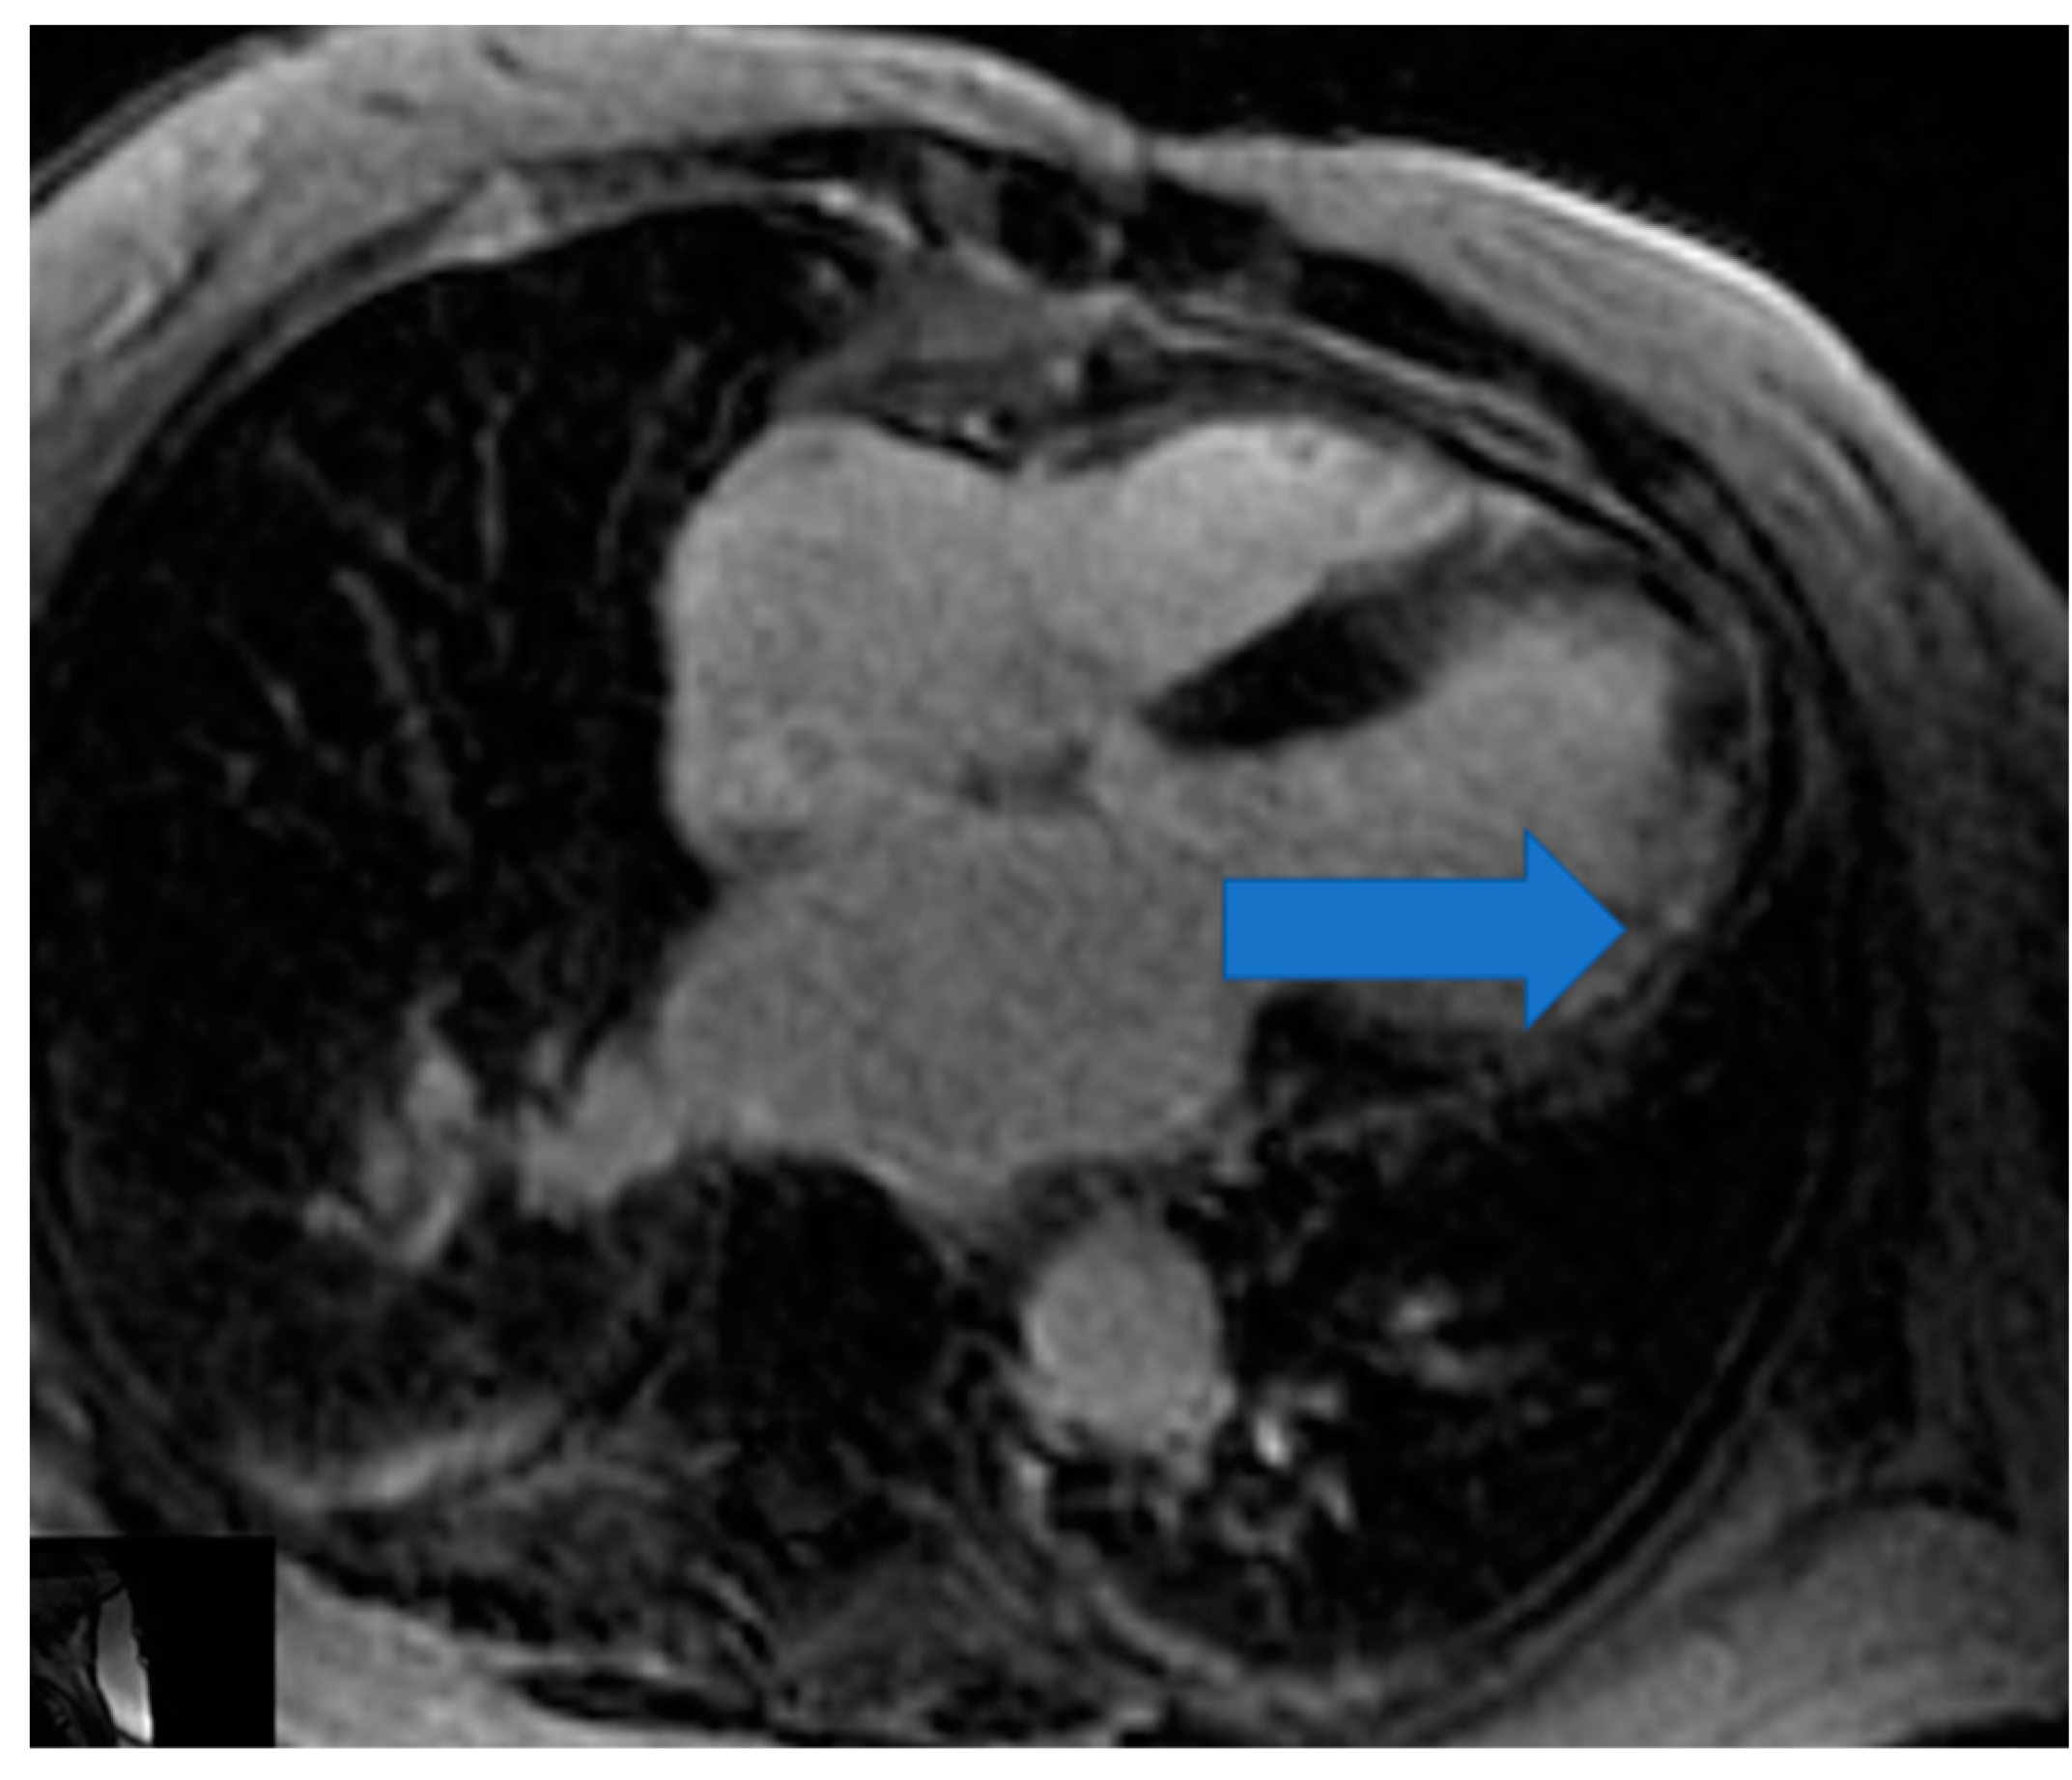

4.1. Biventricular Function Assessment